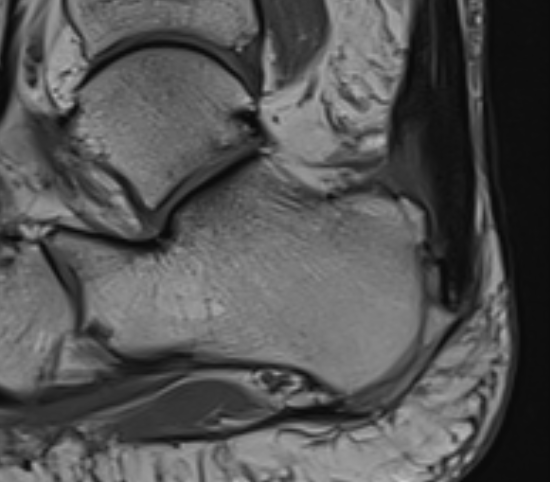

Retrocalcaneal bursitis with Haglund's

Partial tearing at insertion with retrocalcaneal bursa

Tendon thickening, Haglund's deformity and retrocalcaneal bursa

MRI grading

- Grade I: 6 - 8 mm thickening

- Grade II: > 8 mm tendon thickness with < 50% tendon degeneration

- Grade III: > 8 mm tendon thickness with > 50% tendon degeneration